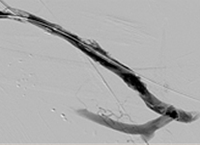

Case CLI with right foot ulcer thrombectomy: Posterior and anterior tibial

Case CLI with Right Foot Ulcer Thrombectomy pre-procedure arteriogram.

Arteriogram of posterior and anterior tibial post-CDT

PT and AT remained occluded following overnight CDT infusion of lytic

Case CLI with Right Foot Ulcer Thrombectomy post-AngioJet Solent Dista.

Post-AngioJet™ Solent™ Dista thrombectomy with PowerPulse™ delivery

AngioJet Solent Dista Catheter used in Power Pulse mode in both AT and PT. 30 min dwell in  AT and 45 min dwell in PT. Followed by Solent Dista Catheter used in thrombectomy mode

Case CLI with Right Foot Ulcer Thrombectomy post-procedure arteriogram.

Post-procedure arteriogram

Image following ballooning of small focal lesion in PT